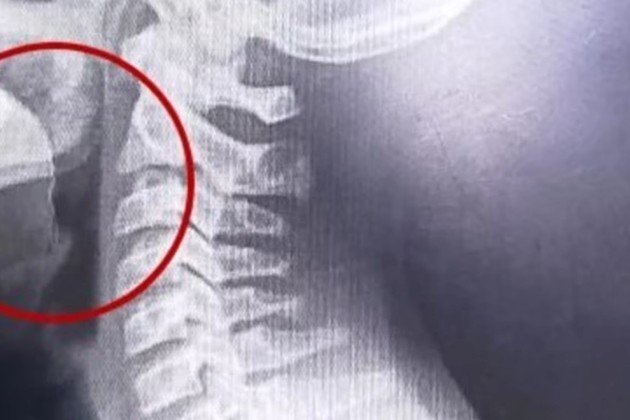

Una vez en el hospital, el enfoque médico cambió. El adolescente fue evaluado de inmediato, internado y sometido a una serie de estudios para determinar el origen del cuadro. Los primeros análisis descartaron infecciones o causas bacterianas, pero la clave apareció con estudios por imágenes.

Las placas revelaron la presencia de un objeto extraño en la vía aérea superior. A partir de ese hallazgo, el equipo médico decidió avanzar con una laringoscopía, un procedimiento que permitió observar directamente la zona afectada.

Durante la intervención, los especialistas detectaron un elemento inusual: un alambre fino que se encontraba incrustado en la garganta del adolescente. Este objeto habría sido ingerido accidentalmente junto con la galletita, provocando las lesiones internas, el sangrado y la dificultad respiratoria.